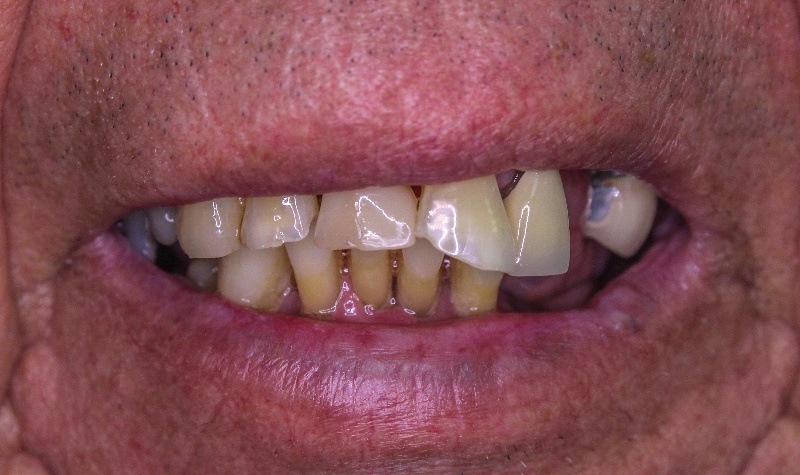

Caso planificado con prótesis híbrida fija completa sobre 4 implantes mandibulares.